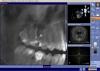

Janine Опубликовано 16 апреля, 2011 Автор Поделиться Опубликовано 16 апреля, 2011 Сделала КТ. теперь думаю, куда податься...Шестерка верхняя правая Ссылка на комментарий

Zoya.111 Опубликовано 16 апреля, 2011 Поделиться Опубликовано 16 апреля, 2011 Здравствуйте! Недавно обратилась к врачу с тем, что у меня постоянно опухает (несильно) десна, и беспокоят неприятные ощущения. С этим я не раз обращалсь к разным стоматологам. Никто не мог найти причину. На снимках все в порядке. Однако, в этот раз, девушка сама могла увидеть припухлость. Сделали рентген с разных ракурсов ( к сожалению, выпросить у них снимки я не догадалась). Сам зуб не болит и не болел. Зуб депульпирован 9 лет назад. На снимках ничего такого...правда, при более детальном рассмотрении, врач обнаружила в середине канала (вокруг) как бы мешочек. И сказала, что это должно быть, внутрекорневая резорбция. Стали вксрывать зуб. В одном из каналов было больно. Поставили лекарство, временную пломбу. Десна (не зуб) начала ныть. Но длилось это один день. Вскоре я снова пришла на прием. Сказали, что опухоль уменьшилась, но не прошла. Снова вскрыли, стали чистить каналы. И когда из шпритца стали вливать лекарство в больной канал, я испытала дикую боль. Было ощущение, что игла прошла сквозь десну, хотя нчиего такого не было. несмотря ни на что, поставили временную пломбу с йодом. Десна начала ныть сильнее. И три дня я сидела на таблетках. Сегодня решила пойти снова без особой надежды на успех(((И мне там сказали,что не могут понять причину воспаления. Сказали. что нужно сделать КТ. Я попросила вскрыть пломбу, надеясь, что боль утихнет. Вот, сижу с открытым зубом, и десна БОЛИТ!!! Полощу содой с солью. Не знаю, что и делать. Ни в КТ, ни в стоматолога не верю. Что же это может быть? Может быть, мне другого доктора поискать или смысла нет? Разберется ли другой доктор... Евгения, Санкт-Петербургв переднем щечном перфорация где то в середине .в каналах пусто Ссылка на комментарий

Kivilgar Опубликовано 16 апреля, 2011 Поделиться Опубликовано 16 апреля, 2011 в переднем щечном перфорация где то в середине Очень похоже. Ссылка на комментарий

Kivilgar Опубликовано 16 апреля, 2011 Поделиться Опубликовано 16 апреля, 2011 Всем спасибо за ответы!Я так понимаю, полное удаление зуба?...КТ что вы разместили не очень разборчива, чтоб более точно утверждать еще варианты есть? Ссылка на комментарий